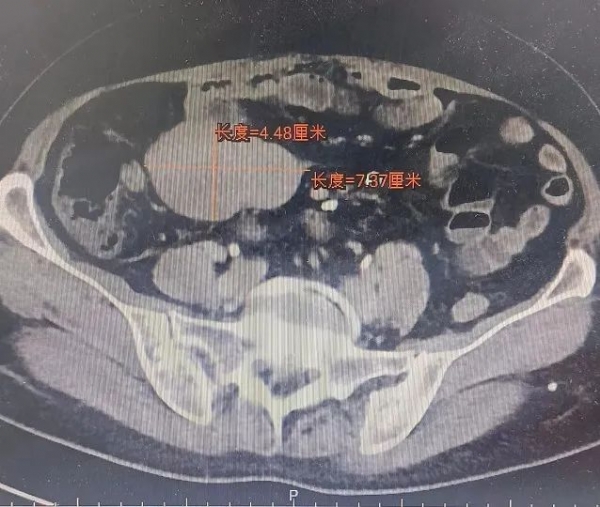

案例二:本市的刘女士,因“小肠间质瘤术后3年余,右下腹痛3天”来我院就诊。询问病史得知:患者于3年前曾因“小肠间质瘤”与外院行开腹手术治疗,术后服用“甲磺酸伊马替尼”1年多自行停药,未再定期复查。之后患者间断出现恶心、呕吐不适,3天前再次出现恶心、呕吐不适,并出现腹痛。腹部CT结果提示:患者右下腹有个7.5×4.5cm大小的肿瘤。考虑为小肠间质瘤复发。

腹部CT检查所示: